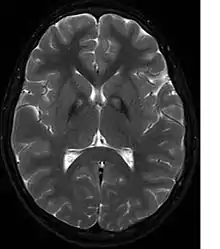

A neurological examination would show evidence of muscle rigidity; weakness; and abnormal postures, movements, and tremors. If other family members are also affected, this may help determine the diagnosis. Genetic tests can confirm an abnormal gene causing the disease. However, this test is not yet widely available. Other movement disorders and diseases must be ruled out. Individuals exhibiting any of the above listed symptoms are often tested using MRI (Magnetic Resonance Imaging) for a number of neuro-related disorders. An MRI usually shows iron deposits in the basal ganglia. Development of diagnostic criteria continues in the hope of further separating PKAN from other forms of neurodegenerative diseases featuring NBIA.

Microscopic features of PKAN include high levels of iron in the globus pallidus and the pars reticulata of substantia nigra, evident as a characteristic rust-brown discoloration[6] in a pattern called the eye-of-the-tiger sign;[7] lipofuscin and neuromelanin concentrated in the iron-accumulating areas; oval, nonnucleated structures representing swollen axons whose cytoplasm swells with vacuoles, referred to as spheroids, axon schollen, or neuroaxonal dystrophy; and Lewy bodies.[6]